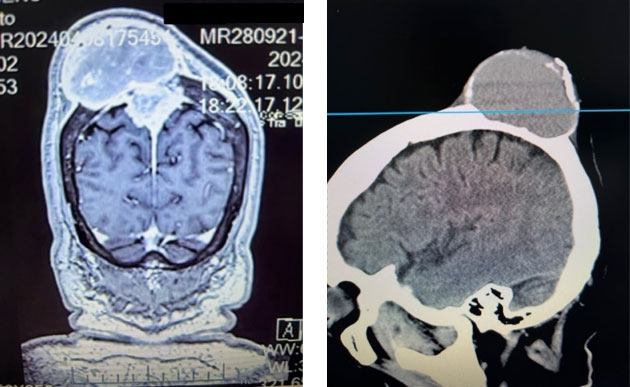

在家人的陪同下,陈阿姨来到广东省人民医院神经外科就诊,经评估,肿瘤巨大,近8cm,颅内部分位于功能区,且侵犯了重要的矢状窦血管,分隔左右大脑的大脑镰也有受累及,颅外部分已经破坏颅骨,明显挤压头皮,扩张隆起,初步评估为脑膜瘤。

脑膜瘤虽大多数都是良性,但如此复杂的情况处理起来有相当难度,既要尽可能全部切除肿瘤,又要重点保护功能区脑组织和正常的矢状窦血管,还要修补缺损的颅骨,同时还要考虑到将扩张的头皮进行塑形,避免术后出血和积液以及伤口感染等。

甘武副主任医师、林晓风主任医师团队经过充分评估和术前准备,按计划进行手术,手术中将肿瘤连同受累及的颅骨、硬膜、静脉窦、大脑镰一并彻底切除,并完好保护正常脑组织和血管,修补硬膜,个体化定制修补颅骨,头皮塑形,一层层还原,手术非常顺利,出血很少。而且,手术按照陈阿姨的期待,没有剃光头,个体化设计最小切口,将手术的痕迹隐藏。

术后复查显示肿瘤切除很干净,术区没有渗血,没有积液,没有血肿,陈阿姨恢复很好,术后病理也提示为良性脑膜瘤,顺利出院。